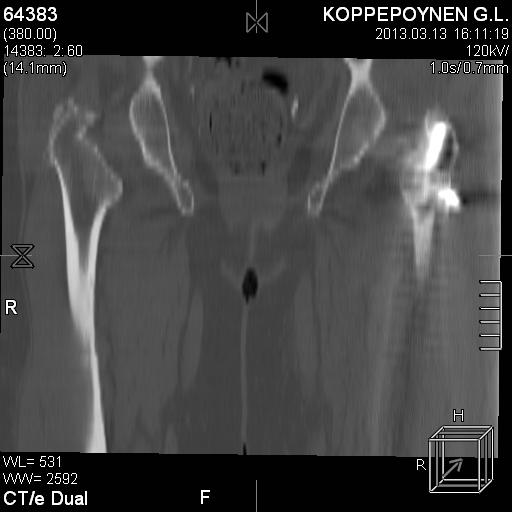

[Ortho] Чрезподвертельный перелом бедра. Остеосинтез стержнем. Перелом металлофиксатора. Дальнейшая тактика?

Делали КТ после операции.